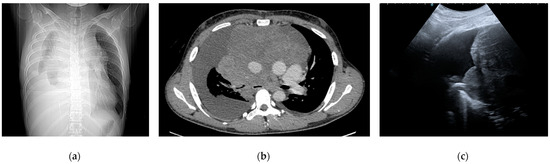

- Yang, P.C. Ultrasound-Guided Transthoracic Biopsy of the Chest. Radiol. Clin. N. Am. 2000, 38, 323–343. [Google Scholar] [CrossRef]

- Rambhia, S.H.; D’Agostino, C.A.; Noor, A.; Villani, R.; Naidich, J.J.; Pellerito, J.S. Thoracic Ultrasound: Technique, Applications, and Interpretation. Curr. Probl. Diagn. Radiol. 2017, 46, 305–316. [Google Scholar] [CrossRef]

- Smargiassi, A.; Inchingolo, R.; Soldati, G.; Copetti, R.; Marchetti, G.; Zanforlin, A.; Giannuzzi, R.; Testa, A.; Nardini, S.; Valente, S. The Role of Chest Ultrasonography in the Management of Respiratory Diseases: Document II. Multidiscip. Respir. Med. 2013, 8, 55. [Google Scholar] [CrossRef] [PubMed]

- Yi, D.; Feng, M.; Wen Ping, W.; Zheng Biao, J.; Fan, P.L. Contrast-Enhanced US-Guided Percutaneous Biopsy of Anterior Mediastinal Lesions. Diagn. Interv. Radiol. 2017, 23, 43–48. [Google Scholar] [CrossRef]